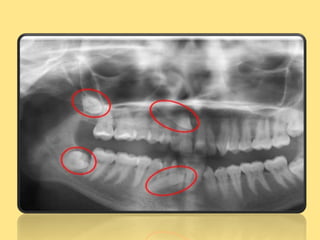

IMPACTED TEETH

Condition of being firmly lodged

(impacted in alveolar bone) or wedged by a

physical barrier ,usually other teeth,so it

is prevented from erupting.

impaction

Etilogy of impaction